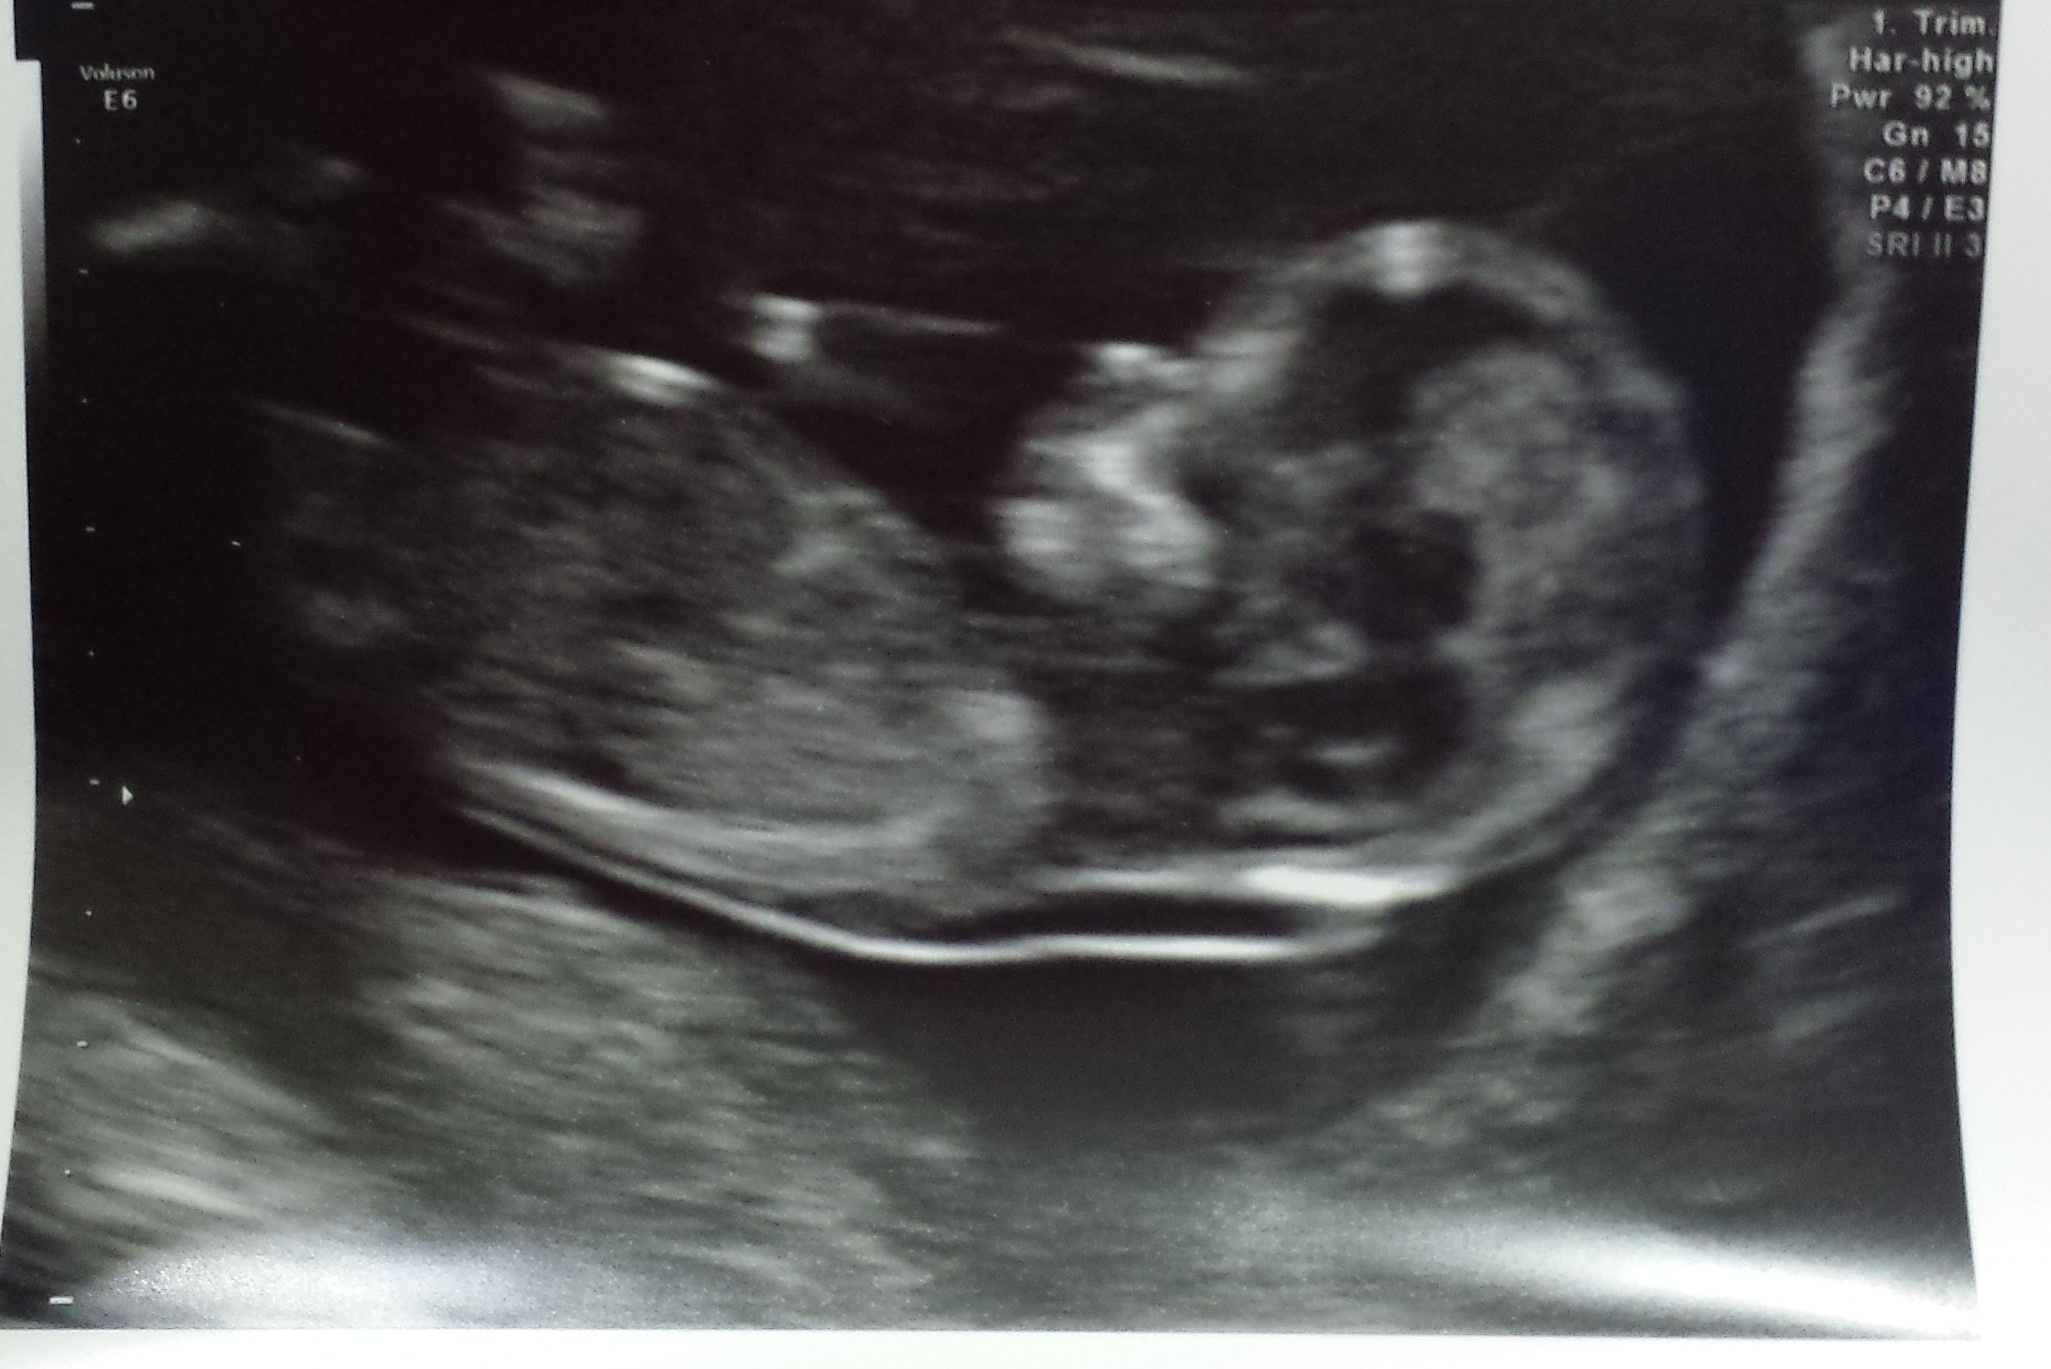

I have only just come across the nub theory and would love if anyone could give me an opinion on my scan at 12weeks and 4days?

I think I can see the nub on the last picture. I'm not very good but would go for a slight girl lean.

I'm not sure the nub is seen in any if the images.

Maybe a girl?